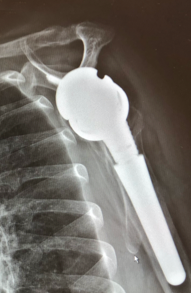

1-year follow-up

Result

- Good stability

- Good function and ROM

- Pain free